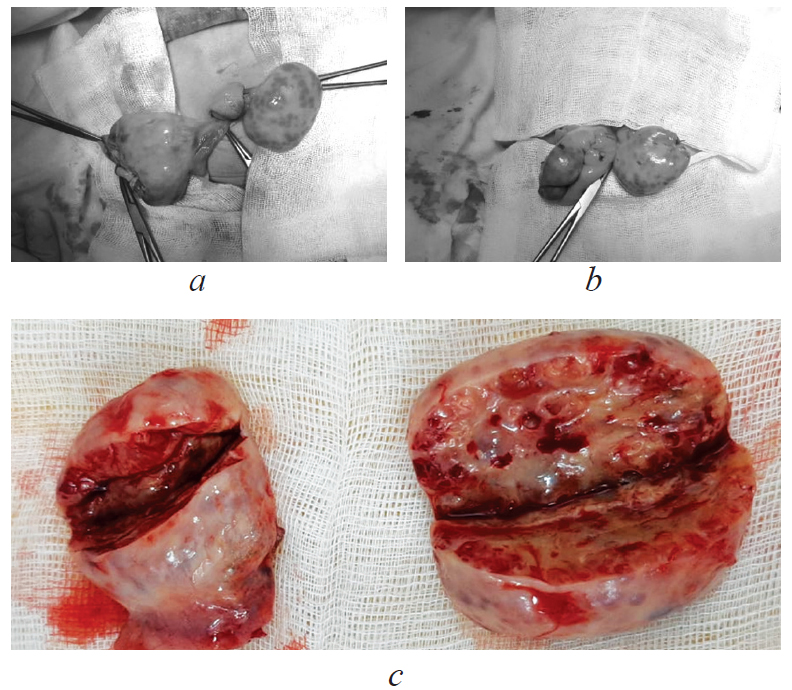

Under aseptic conditions with endotracheal anesthesia, supraumbilical minilaparotomy was performed, with ovarian cyst puncture on the right and resection of both ovaries (Fig. 3). Laparoscopic hernioplasty and umbilical hernia repair were also performed.

Fig. 3. Surgical treatment: a, b — resection of the right ovary; c — macropreparation, resected ovaries

The ovaries measured 4.4 × 3.5 × 2.5 cm on the right and 5.2 × 4.5 × 1.5 cm on the left. On the incision in both ovaries, multiple cysts, with a maximum size of 0.5 × 0.4 cm, were revealed. The histological examination determined multiple follicular cysts lined with multi-row follicular epithelium with pronounced cell proliferation, dystrophic changes, and luteinization phenomena. A wide layer of large theca cells was adjacent to the follicular cysts. The identified morphological changes corresponded to secondary hyperthecosis (Fig. 4).